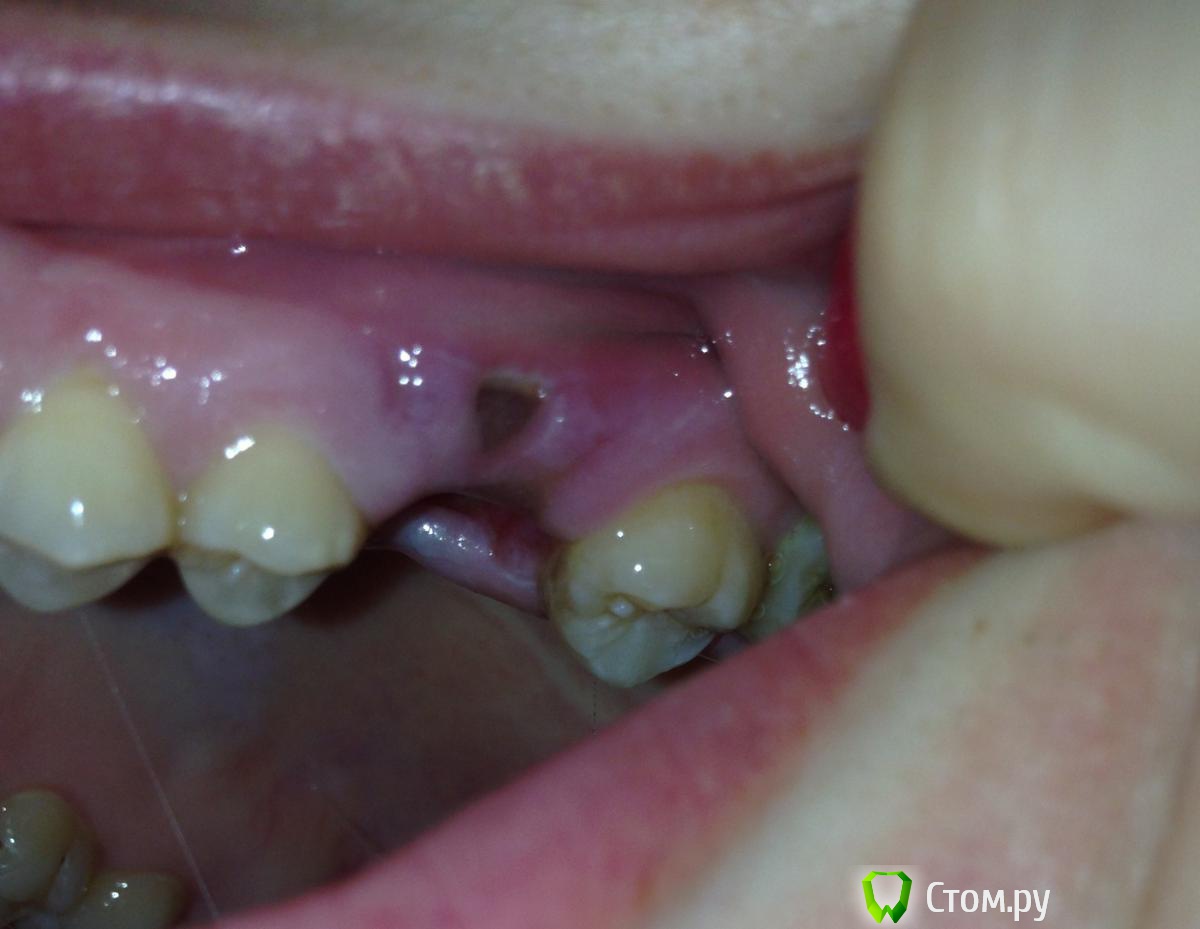

30 мая экстренно удалили 6 зуб сверху. Побежала к незнакомому врачу, т.к. прихватило. Думала вылечит - сказал надо удалять. Зуб депульпирован в 2006 году, с тех пор раз в три года снимали пломбу (которая наполовину отваливалась), лечили кариес, пломбировали снова.

Удаляли долго, минут 40, три корня. Зуб вышел целиком, не сломался. Потом сделали сгусток из крови, которую предварительно взяли из вены, и прилепили туда. Зашили. Врач сказал со следующего дня аккуратно прополаскивать хлоргексидином и пить Кетонал. Вообще толком ничего не объяснил как себя вести. Антибиотиков не назначал. Через три часа началось кровотечение, которое остановилось только на следующий день.

С момента удаления зуба прошло 9 дней. Солкосерил уже бесит, но без него еще хуже. Еще и дырка небольшая появилась в десне после зашивания, на фото видно. Все слишком плохо? Что делать дальше? Нужны ли физио процедуры, антибиотики, что-то еще?

post-39094-0-94300200-1402226493_thumb.jpg